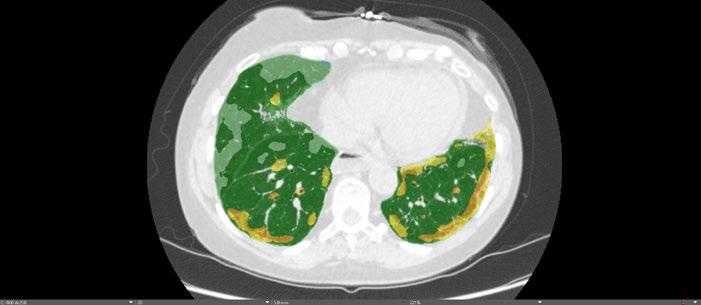

Radiogenomics Relationship of Nonsmall Cell Lung Cancer: Preliminary Results

Keywords: Cancer, lung, radiogenomics, radiology.

BACKGROUND AND AIMS

Radiomics, an emerging paradigm in medical imaging, entails the quantitative analysis of tumour features, and has exhibited potential in predicting treatment responses and outcomes. Furthermore, within the domain of -omics assessments, the significance of comprehensive genetic evaluation in non-small cell lung cancer (NSCLC) is on the rise, influenced by both biological and therapeutic considerations.

The aim of this study was to correlate radiomics features with the genetic results obtained from liquid biopsy in patients with lung tumours. The prediction of tumour genetics in radiomics relies on the presumption of conducting a non-invasive evaluation of molecular characteristics in tumour tissues, which can be challenging in certain tumour types, such as NSCLC. Therefore, in this context, the authors considered it pertinent to explore and generate hypotheses regarding the technical feasibility of identifying associations between genomics acquired through liquid biopsy assessments and radiomics.

MATERIALS AND METHODS

This observational, prospective study integrated radiomic perspectives using CT and genomic perspectives, through next-generation sequencing applied to liquid biopsies.

The authors included 62 patients with NSCLC who underwent pre-surgery CT (Revolution™ 128 MDCT, GE HealthCare, Chicago, Illinois, USA) at the Radiology Department of Campania University Luigi Vanvitelli, Naples, Italy. Every patient for whom liquid biopsy was performed gave informed consent for the genetic analysis. For the radiomic analysis, image processing CT volumes were manually delineated using ITK-SNAP 3.8.0 (University of Pennsylvania, Philadelphia, USA). Radiomics features (first order: Gray Level Co-occurrence Matrix, Gray Level Run Length Matrix, Gray Level Size Zone, Gray Level Dependence Matrix, and Neighbouring Gray Tone Difference Matrix) were computed using Pyradiomics1 in Python 3.7 (Python Software Foundation, USA) environment.

Radiomic features were derived from CT images, and genetic assessments were performed using a comprehensive panel targeting 523 cancerrelated genes. For the statistical analysis, association between radiomic features and gene mutations were assessed using feature importance based on receiver operating characteristic curve analysis; moreover, a machine learning approach based on support vector machine was used to evaluate the ability of radiomic features to predict gene mutations.

Associations between radiomic features and genetic mutations were established using the area under the receiver operating characteristic curve. Machine learning techniques, including support vector machine classification, aimed to predict genetic mutations based on radiomic features. The prognostic impact of selected gene variants was assessed using Kaplan–Meier curves and log-rank tests.

RESULTS

Sixty-two patients underwent screening, with 53 being comprehensively characterised radiomically and genomically. This group was predominantly male (68.4%), and adenocarcinoma was the prevalent histological type (73.7%). Most patients exhibited ECOG Performance Status of 0 or 1 (87.7%), and 91.2% had a history of former or current smoking. Disease staging was distributed across I–II (38.6%), III (31.6%), and IV (29.8%). Significant correlations were identified with mutations

Abstract ● ECR 2024 24 Radiology ● April 2024 ● Creative Commons Attribution-Non Commercial 4.0

of ROS1 p.Thr145Pro (shape_Sphericity), ROS1 p.Arg167Gln (glszm_ZoneEntropy, firstorder_TotalEnergy), ROS1 p.Asp2213Asn (glszm_GrayLevelVariance, firstorder_ RootMeanSquared), and ALK p.Asp1529Glu (glcm_Imc1). Patients with the ROS1 p.Thr145Pro variant demonstrated markedly shorter median survival compared to the wild-type group (9.7 months versus not reached; p=0.0143; hazard ratio: 5.35; 95% confidence interval: 1.39–20.48).

CONCLUSION

This study contributes to advancing the prediction of cancer genetics through the application of non-invasive radiomic techniques. The prediction of tumour genetics in radiomics hinges on the assumption of conducting a non-invasive assessment of molecular characteristics in tumour tissues, which can pose challenges in certain tumour types, such as NSCLC. Therefore, within this context, the authors deemed it relevant to explore and formulate hypotheses regarding the technical feasibility of identifying associations between genomics obtained through liquid biopsy assessments and radiomics.

Specific radiomic features illustrate the capability to predict non-synonymous mutations of ROS1 and ALK in patients with NSCLC. Investigating the prediction of cancer genetics using non-invasive radiomic techniques represents an innovative frontier in scientific research, which is currently undergoing extensive investigation. Research on the use of conventional CT features and CT image-based radiomic features to predict the gene mutation status of lung cancer is still in its nascent stages.

The integration of radiomic techniques in predicting cancer genetics holds potential, but is constrained by cost and technological limitations. Despite these challenges, the authors’ study explores the relationships between genomics and radiomics, revealing specific genetic variants associated with radiomic features. While acknowledging limitations, particularly the small sample size and the lack of actionable mutations, this research lays the groundwork for broader investigations aiming to link radiomics and genomics in NSCLC. The ultimate objective is to improve prognostic accuracy and refine therapeutic strategies. ●